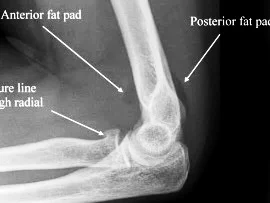

X-ray

- A visible posterior fat pad on the lateral view of the elbow is a sign of occult intra-articular trauma